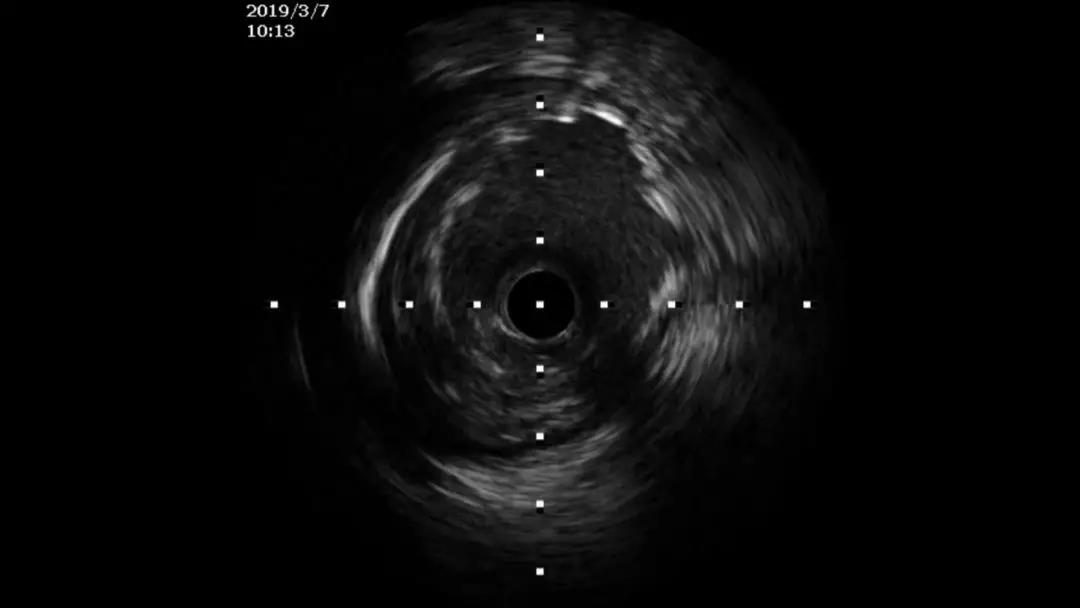

2019年3月7日,冠脉造影和IVUS评估:

左冠TIMI血流3级

送人IVUS导管,进行IVUS检查

IVUS提示支架部分节段贴壁不良

合适直径球囊,高压后扩

再次造影和IVUS,支架贴壁良好